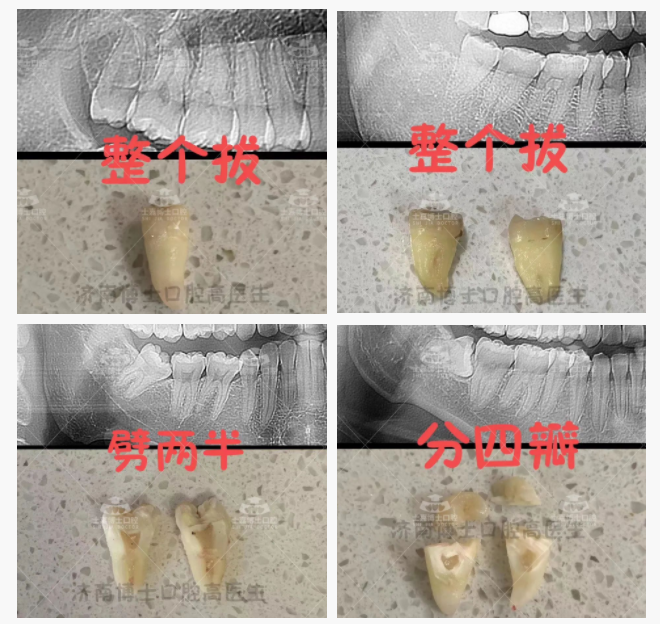

但对于更多的长歪的智齿来说,拔牙可不仅仅是「拔」的本意,更可能是「磨」牙、「挺」牙、「劈」牙、「敲」牙……

比如这种:

这可怎么拔出来?

舒适拔除后:

还有更多难度更大的阻生齿拔除比如近中阻生智齿、低位阻生(牙根靠近下牙槽神经管)的智齿,甚至需要更专业的医生和更高超的技术,搭配先进仪器,才能将智齿「拔出来」。